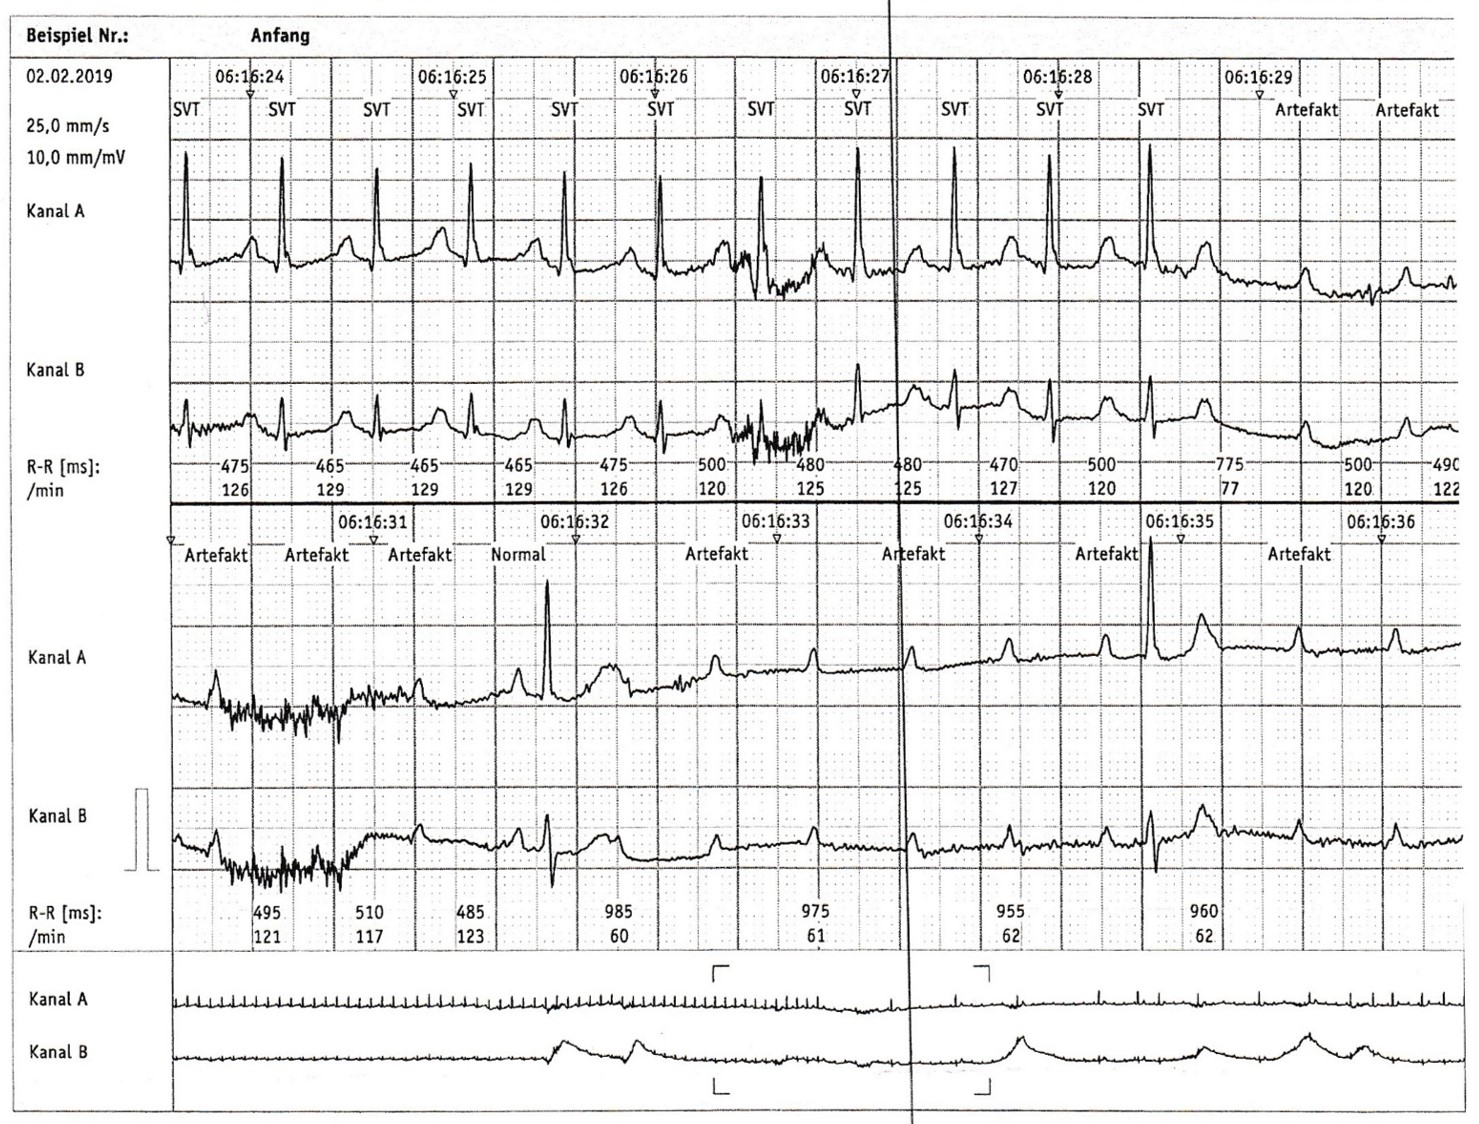

(PDF) Atrioventrikuläre Blöcke

Daher kann die Erscheinung einer unspezifische intraventrikuläre Leitungsstörung ziemlich nuanciert sein.Anhand des Sitzplans des FC Bayern München finden Sie ganz einfach ihren Platz in der Allianz Arena. Vorhoftachykardie.Leitungsverzögerung: AV-Blöcke, Schenkelblöcke, Faszikelblöcke.Atrioventrikuläre Überleitungszeit ( AV-Zeit) Atrioventrikularklappe.PDF | On Jun 19, 2019, Jrg Schlpfer and others published Atrioventrikuläre Blöcke | Find, read and cite all the research you need on ResearchGate 9 2 Diskrete Verzögerung der rechtsventrikulären Erregungsausbreitung. Es gibt zwei getrennte Rhythmen, der Sinusknoten erregt die Vorhöfe, der Rhythmus aus dem Bereich des AV-Knotens erregt die Kammer. Die Adresse der Allianz Arena lautet Werner-Heisenberg-Allee 25, 80939 München.Bei einem AV-Block ist die Überleitung der Erregung vom Vorhof über den AV-Knoten auf die Kammern gestört. Die häufigste Ursache ist eine idiopathische Fibrose und Sklerose des Erregungsleitungssystems. bei einem persistierenden AV-Block II.